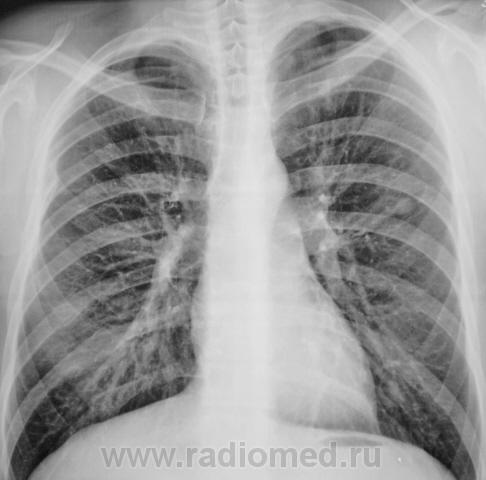

Туберкулома? | Портал радиологов